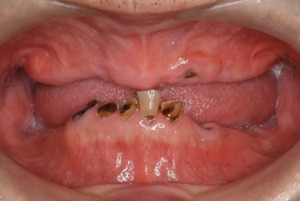

05

長く使える入れ歯を

作っていきます。

ご病気などで歯茎が痩せてしまうことがあります。そんなとき、当院では中側の歯茎の部分に裏打ちをして、またお使いできるように体制を整えています。